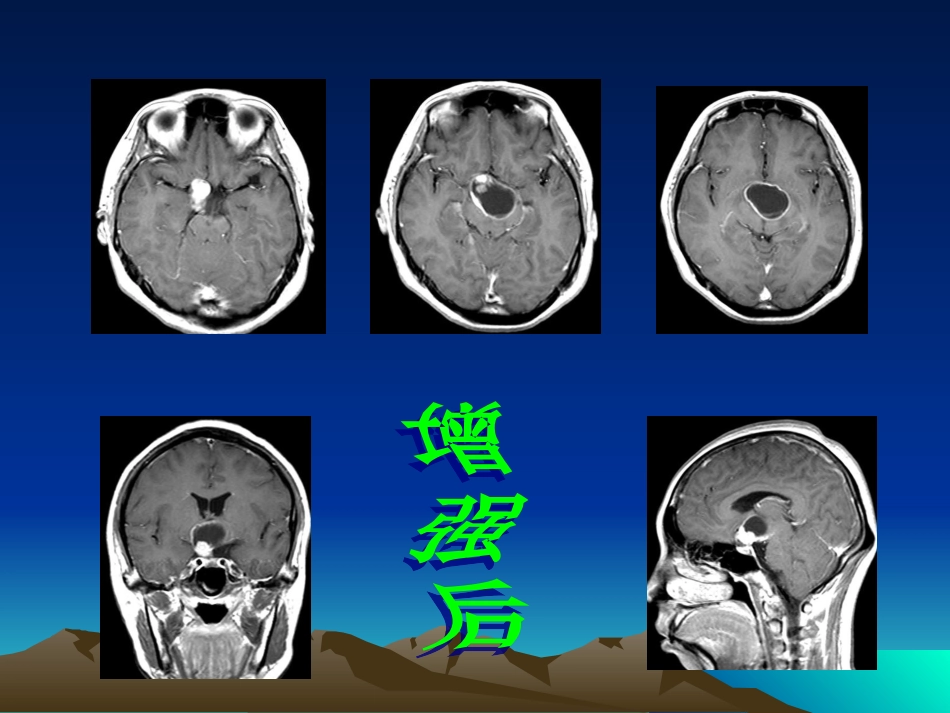

患者,女,30岁,停经泌乳半年,视物不清2月伴多饮多尿患者,男,13岁双眼视力下降多年偶有头痛颅咽管瘤的影像诊断颅咽管瘤的影像诊断概论概论•是儿童颅内最常见的非胶质来源的肿瘤•仅次于垂体腺瘤,是鞍区第2常见肿瘤•约占鞍区肿瘤的30%•来源于原始口腔形成过程中的拉氏袋(Rathke’spouth)的残余,主要分布于垂体结节部及漏斗附近发生率发生率•占颅内肿瘤的1.2-4%,占儿童颅内肿瘤的6-9%,约占儿童鞍区及视交叉肿瘤的54%•男女比率约为1:1•青少年多见,患病年龄高峰为10岁左右(5-15),另外一个高峰期为大于65岁好发部位好发部位•鞍上型约占75%•鞍上及鞍内型多见,约占21%•鞍内型极少见,主要见于成人,约占4%•经常延伸至多个颅窝病理特点病理特点•囊变单囊或多囊,囊变区多位于瘤体上部•钙化囊壁、瘤体的实性部分可发生钙化,钙化的发生率约为70%•实性10%病理类型病理类型•牙釉质型大多数,多见于青少年,肿瘤主要由鳞状上皮细胞组成,囊内含大量胆固醇和机油状内容物,多数肿瘤与脑组织界面不规则,手术不易剥离•乳头型几乎仅见于成人,肿瘤缺乏钙化及机油状内容物,囊壁由纤维血管乳头构成,并被覆单层鳞状上皮,肿瘤与脑组织界面较光整,手术易于全部切除临床表现临床表现•根据病灶位置、病灶大小、病人年龄不同而临床表现不同•颅内压增高肿瘤突入第Ⅲ脑室,导致脑积水,最常见于儿童•视力、视野损害视神经通路受阻所致•垂体机能低下•下视丘症状视丘下部受累所致,尿崩症、体温低下、嗜睡及肥胖性生殖无能、停经-泌乳综合征•精神症状•其他颅神经损害症状影像学诊断影像学诊断•X线平片•CT•MRIXX线平片表现线平片表现•肿瘤的直接征象囊壁的钙化,点状、斑块状、薄片状或蛋壳状;位于鞍内或/和鞍外、鞍上或鞍后•肿瘤的间接征象蝶鞍变扁、前后径增大,后床突骨质吸收CTCT表现表现牙釉质型:•90%为混杂密度•90%伴有钙化•90%有强化(结节或环状强化)乳头型:实性、等密度、钙化罕见患者,女,42岁,闭经4年,头痛1天MRIMRI表现表现•信号特点复杂,内容物不同信号不同MRI信号特点CT密度特点病理T1WI/T2WI均为高信号低密度水化胆固醇结晶或/和正铁血红蛋白T1WI低信号,T2WI为高信号低密度囊性坏死,且蛋白质含量高T1WI/T2WI均为低信号高密度大量角化蛋白和骨小梁网T1WI等信号,T2WI为高信号等密度缺乏胆固醇及正铁血红蛋白诊断要点诊断要点•CT儿童鞍上肿块,伴有钙化和囊变•MR复杂信号的鞍上肿块•当MR不能确诊时,用平扫CT来寻找钙化鉴别诊断鉴别诊断•垂体腺瘤•胶质瘤•其他神经节细胞瘤脊索瘤鞍区上皮样囊肿或皮样囊肿垂体腺瘤垂体腺瘤•青春期前的儿童罕见•极少发生钙化•蝶鞍呈球形扩大•鞍底骨质受侵无钙化的颅咽管瘤与垂体腺瘤鉴别困难胶质瘤胶质瘤•毛细胞星形细胞瘤可发生于视交叉,偶可有钙化及囊变神经节细胞瘤神经节细胞瘤•好发于颞叶,但亦可见于第Ⅲ脑室及丘脑下部,个别与颅咽管瘤鉴别困难脊索瘤脊索瘤•好发于斜坡,可钙化,极少囊变,局部骨质破坏为其显著鉴别要点鞍区上皮样囊肿或皮样囊肿鞍区上皮样囊肿或皮样囊肿•囊性占位,钙化发生率低•囊壁极少有强化病程和预后病程和预后•通常为缓慢生长的良性肿瘤•小于5cm的肿瘤的复发率约为20%•大于5cm的肿瘤的复发率约为83%•十年生存率约为64-96%治疗和预后治疗和预后•手术治疗鞍内型及视交叉型易全部切除视交叉后型、脑室型难以根治•放射治疗外放射或内放射